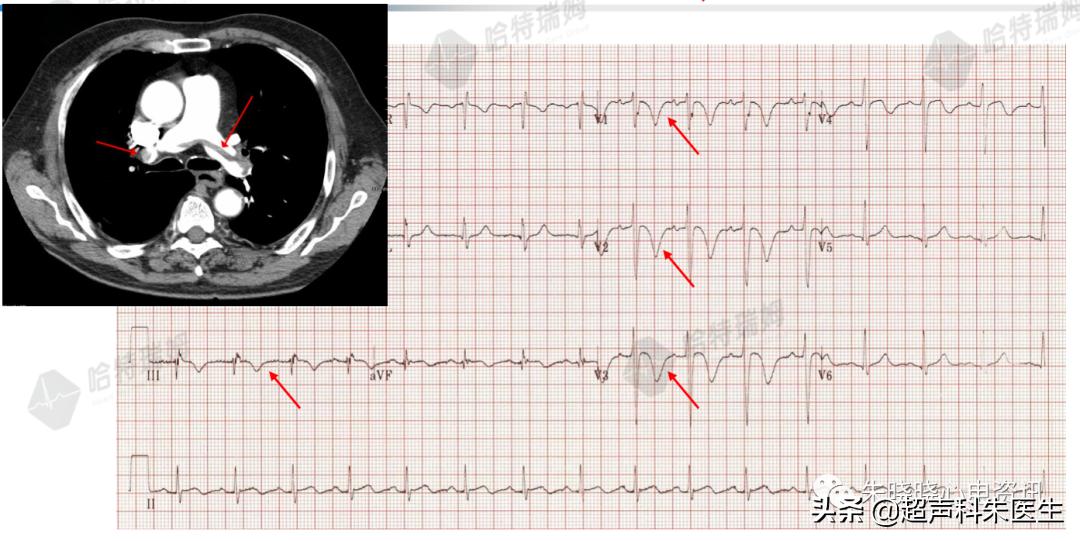

病例7:肺栓塞

急性肺栓塞引起的T波倒置,最常发生在右胸V1~V3导联,常有III导联并存;T波多呈双支对称性倒置,多在急性肺栓塞后1~2个小时发生,随着病情的发展呈动态变化。

图25:肺栓塞与T波倒置

其机制可能为:其一,急性肺栓塞时右室压力负荷迅速增加,导致右室扩张及收缩、舒张功能不全,引起牵张力增加,使T波倒置;其二,肺栓塞也可导致右室心外膜下急性心肌缺血,形成T波倒置。